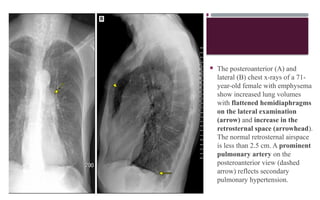

 The posteroanterior (A) and

lateral (B) chest x-rays of a 71-

year-old female with emphysema

show increased lung volumes

with flattened hemidiaphragms

on the lateral examination

(arrow) and increase in the

retrosternal space (arrowhead).

The normal retrosternal airspace

is less than 2.5 cm. A prominent

pulmonary artery on the

posteroanterior view (dashed

arrow) reflects secondary

pulmonary hypertension.